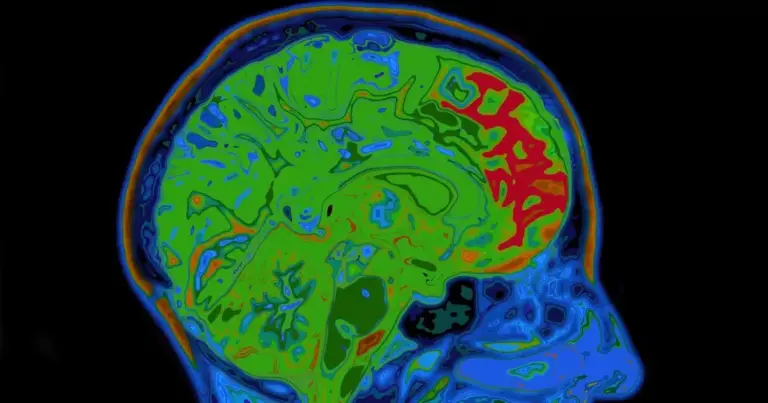

Dein Gehirn schrumpft in den Wechseljahren – und das hat nichts mit Vergesslichkeit zu tun

Du kennst die Hitzewallungen und die Stimmungsschwankungen. Vielleicht kämpfst du mit Schlafstörungen. Aber hast du darüber nachgedacht, was wirklich mit deinem Kopf passiert, wenn die Hormone verrücktspielen? Ich sage dir jetzt etwas, das du nicht ignorieren darfst: Wissenschaftler fanden heraus,…